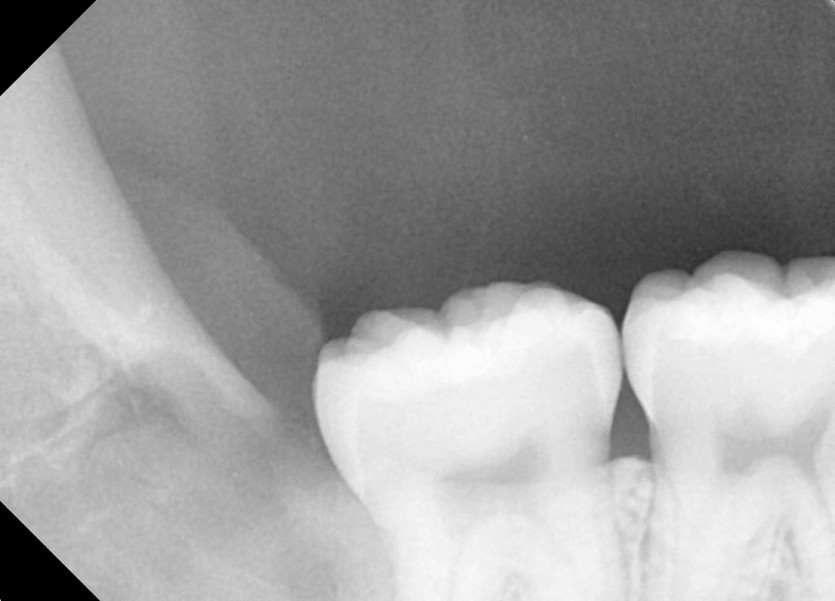

#48 사랑니 발치

구강 외과 전문의가 당일 발치했습니다.